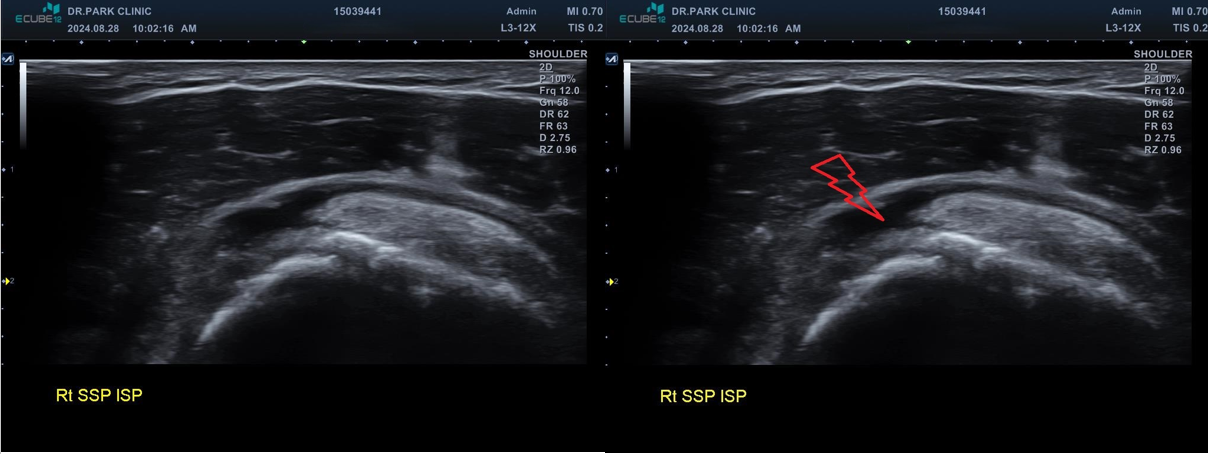

극상근 전층파열이 의심됩니다. 빨간색 번개 부분

마지막 초음파에서는 어깨 극상근의 파열 소견이 관찰되고 있습니다. 정확한건 mri 를 찍어봐야 하겠지만 찢어진 길이와 정도로 봐서는 수술이 필요한 극상근 전층파열로 생각이 됩니다.